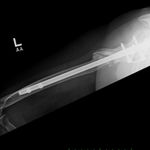

She was advised of the need to do some sort of stabilization which is necessary since the use of low-dose ultrasound has not helped in the healing process. She was unwilling to have any further operative intervention and sought further options. Eventually, she agreed to a fourth procedure of intra-medullary nail stabilization of the fracture and had this carried out in April 2011. An intramedullary nail was inserted in an antegrade manner and she has since gone on to heal the fracture site completely and has regained most of the function of the upper limb with no pain.